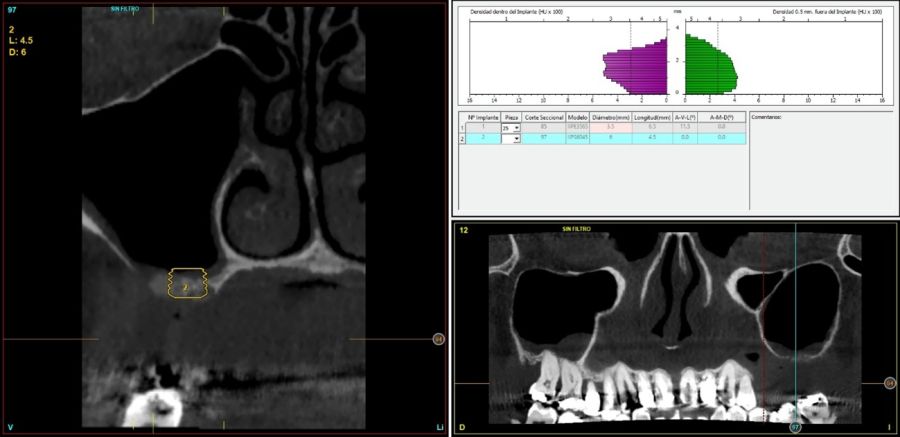

Fueron reclutados de forma retrospectiva pacientes en los que se llevase a cabo una inserción de implantes dentales de 4,5 mm de longitud en crestas óseas residuales de hasta 4,5 mm de altura con elevación de seno transcrestal, utilizando como material de injerto hueso autólogo obtenido del fresado y PRGF-Endoret, unido a la inserción directa con anclaje en la cortical desde junio de 2020 hasta septiembre de 2021. Antes de la colocación de los implantes, todos los pacientes fueron evaluados mediante modelos diagnósticos, exploración intraoral y un CBCT (Cone Beam Computed Tomography), cuyo análisis se realizó con un software especializado (BTI-Scan III), para conocer la altura exacta de la cresta ósea residual y la densidad, y poder adaptar en consecuencia el protocolo y el implante a colocar. Como protocolo preoperatorio, se administró una premedicación antibiótica con amoxicilina (2 g por vía oral) una hora antes del procedimiento, junto con paracetamol (1 g por vía oral) como analgésico. Tras la intervención, los pacientes continuaron con un tratamiento antibiótico de amoxicilina (500-750 mg por vía oral cada 8 horas, según el peso) durante cinco días. La colocación de los implantes fue realizada por un mismo cirujano utilizando la técnica de fresado biológico, caracterizada por bajas revoluciones y ausencia de irrigación, ajustando el procedimiento a la densidad y volumen del lecho óseo receptor para asegurar una adecuada estabilidad primaria del implante8-9.

En todos los casos se realizaron elevaciones óseas desde los 0,2 hasta los 1,3 mm. En la Figura 2 se observa la altura ósea inicial y final para cada uno de los implantes. Las posiciones más frecuentes de los implantes incluidos en el estudio fueron en 16 y en 26 con 33,3% respectivamente, y la menos frecuente en posición 27 (11,1%). Todas las posiciones se muestran en la Figura 3.

El diámetro de los implantes osciló entre los 3,75 mm y los 6 mm, siendo el más frecuente 4,25 mm y 4,75 mm con un 27,8% para cada grupo. Todos los implantes colocados fueron de 4,5 mm de longitud. Los diámetros y longitudes de los implantes incluidos en el estudio en función de la posición se muestran en la Figura 4.

El tipo óseo más frecuente en las zonas de inserción de los implantes fue el tipo IV en el 46,7% de los casos con una densidad media de 263,89 Hu (+/- 134,82). En la Figura 5 se muestran las densidades de todos los implantes en función de la posición y el diámetro.

El torque de inserción de los implantes varió desde 5 Ncm hasta 60 Ncm con una media de 28,33 Ncm (+/- 17,65), siendo el más frecuente 15 Ncm (en el 27,8% de los casos). En la Figura 6 se muestran los torques de inserción logrados en función de la densidad ósea en unidades Hounsfield.

En las Figuras 7- 13 se muestra uno de los casos incluidos en el estudio.